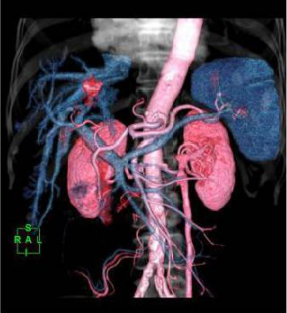

在整體的影像鏈環節進行了改進确保高清晰的圖像。實現了圖像的各向同性,任意方向的 MPR 圖像具有相同的圖像質量。